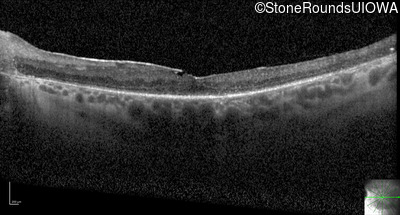

Optical Coherence Tomography - Right - 20/125

Exemplar / OCT Stack